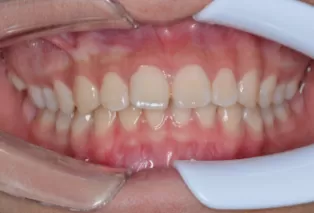

Intraoral photos after treatment